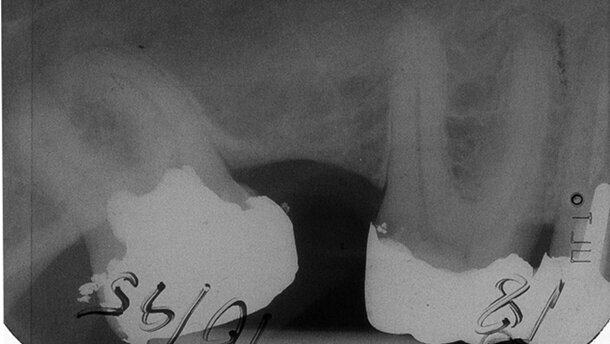

Fisch [16] publizierte 1.933 Spätresultate der Pulpaamputation an 600 Zähnen mit dem Formaldehydpräparat Triopaste. Die Kontrollen erfolgten 6 Monate bis zu 18 Jahre nach Amputation. 9% wiesen bei der Röntgenkontrolle einen pathologischen Apex auf. 11 extrahierte Zähne konnten histologisch untersucht werden. Hartsubstanzbildung wurde nachgewiesen in Form eines Verschlusses des Foramen apicale und Apposition an den lateralen Kanalwänden, die z. T. bis zur Obliteration des Kanallumens führte. Overdiek [17] testete N2 als formaldehydhaltiges VitA-Mittel an Humanzähnen im Kurzzeitversuch bis zu zweieinhalb Monaten. Er stellte fest, dass mehrere Wochen nach N2-Applikation die Möglichkeit der Entwicklung einer Hartsubstanzbarriere bestünde. Stern führte während einer Periode von 12 Jahren unter relativer Trockenlegung 175 Pulpotomien mit N2 an Zähnen mit abgeschlossenem Wurzelwachstum durch, unabhängig von eventuellen anamnestischen Schmerzen. 15% der Patienten/-innen hatten nach der Behandlung stärkere Beschwerden, die innerhalb von 48 Stunden abklangen. Jedoch hätten 4 Patienten/-innen eine Pulpitis entwickelt mit der Folge der Extraktion von 3 Zähnen und der konservativen WKB eines Zahnes. Stern war in der Lage, das Schicksal von 35 vitalamputierten Zähnen länger zu verfolgen. Im Laufe der Nachbeobachtung wurden 2 Zähne extrahiert – davon einer wegen Fraktur. 5 Jahre nach Behandlung beobachtete Stern anhand der Röntgenbilder eine fortschreitende Verkalkung der Nervkanäle.

In der Wurzelkanalpräparation wurde nach der N2-Methode [20] vorgegangen: relative Trockenlegung, keine Wurzelkanalspülungen, Wurzelkanalpräparation ausschließlich mit Reamern. Für die Wurzelkanalfüllung (WF) wird sahnig gemischtes N2 mittels Lentulo appliziert. VitA-Kavitäten werden bis 1-2mm in die Kanaleingänge hinein präpariert. Relativ fest gemischtes N2 wird mittels Füllinstrument in die Kavität eingebracht und mit Watte leicht angedrückt. Eine leichte Blutung ist gegenstandslos. Bei stärkerer Blutung wird das eingebrachte N2 nach einigen Minuten entfernt und dann wieder ersetzt. Ein Kunststoffverschluss der Kavität in derselben Sitzung setzt eine Unterfüllung voraus, die bei einem Amalgamverschluss nicht notwendig ist. Die späteren Röntgenkontrollaufnahmen (im Folgenden mit Rö abgekürzt) wurden vom Autor mit einer zweifach und siebenfach Vergrößerungsoptik gesichtet. Der apikale Zustand wurde differenziert nach apikal o.B., apikal fraglich/unsicher und apikal pathologisch. Bewertet wurde stets die Wurzel mit dem schlechtesten Apikalbefund, was auch für die Einstufung der Wurzelkanalfüllgrade galt. Misserfolge ohne begleitende Röntgenaufnahme wurden als Mi1 bezeichnet, Misserfolge mit begleitender Röntgenaufnahme als Mi2. Die prozentuale Gesamtmisserfolgsquote wurde nicht ermittelt durch eine einfache Addition von Mi1 und Mi2, sondern indem der Anzahl der gemachten Rös die Anzahl der Mi1 hinzugefügt wurde. Von dieser Summe wurde der Prozentsatz der subsumierten Misserfolge bestimmt.

47,6% der VitA- und 52,4% der VitE-Patienten/-innen waren männlichen Geschlechts. 70,1% (n = 498) der VitA- und 49,1% (n = 418) der VitE-Patienten/-innen wurden vom Praxisinhaber, die anderen vom Praxismitarbeiter behandelt. Das durchschnittliche Alter der VitA-Patienten/-innen betrug 34,6 Jahre, das der VitE-Patienten/-innen 30,6 Jahre. Der durchschnittliche Beobachtungszeitraum bei VitA lag bei 53,8 Monaten (max. 165), bei VitE bei 49,4 Monaten (max. 169). Von den 710 VitA-Fällen wurden 504 (71%), von den 852 VitE-Fällen 496 (58,1%) einer späteren Röntgenkontrolle unterzogen. Insgesamt wurden 61 VitA-Misserfolge und 77 VitE-Misserfolge registriert. Diese wurden differenziert nach „ohne Begleit-Rö (Mi1)“ und „mit Begleit-Rö (Mi2)“. 51 der 61 VitA-Misserfolge und 63 der 77 VitE- Misserfolge wurden nachgeröntgt. Nicht alle Begleit-Rö’s der Mi2-Misserfolge wiesen einen Misserfolg aus. 2 Begleit-Rös der VitA-Misserfolge und 10 Begleit-Rös der VitE- Misserfolge waren falsch negativ beurteilt worden. Den 10 VitA-Mi1-Fällen folgten ausschließlich Extraktionen wegen Schmerzen – davon 3 nur einige Stunden nach VitA. In 2 Fällen lag in der Kartei der Hinweis auf ein Granulom an einer extrahierten Wurzel vor, in 2 weiteren Fällen folgte die Ex-traktion nach 6 und 11 Tagen. Bei den 16 VitE-Mi1-Fällen wurde 12- mal (1 Tag bis 21 Monate nach VitE) wegen Schmerzen extrahiert. Bei den Patienten/-innen, die nach der VitA-Behandlung wieder die Praxis aufsuchten, lag 240-mal ein positiver und 153-mal ein negativer Hinweis auf eine anamnestische Schmerzsymptomatik vor. Die Misserfolgsrate betrug im ersteren Fall 10,8% (n = 26), im letzteren Fall 7,2% (n = 11).

Ohne Berücksichtigung von Einzelheiten wie Indikationsbreite, anamnestischer Symptomatik, Zahnposition und WF-Grad bei VitE betrug die Gesamt-Misserfolgsrate bei VitA 11,9%, bei VitE 15%. Die VitE-Misserfolgsrate des WF-Grades –3, –4 entsprach genau der VitA-Misserfolgsrate von 11,9%.

Ein direkter Vergleich der VitA zur VitE, insbesondere zur unvollständigen WF nach VitE, ist nur mit Einschränkung zulässig, da das VitA-Kontingent vorwiegend aus einer Negativauslese bestand, das alternativ der Zange überantwortet worden wäre. Auf diese ungünstige Ausgangssituation ist die doppelt so hohe Extraktionsfrequenz der VitA-Zähne im Vergleich zu den VitE-Zähnen zurückzuführen (28,6% vs. 14,4%). Der Extraktionsgrund „frakturiert, zerstört“ machte bei der VitA den hohen Anteil von 51,9% aller Extraktionen aus, bei der VitE 46,3%. Dagegen betraf der Extraktionsgrund „Misserfolg“ (röntgenologisch oder klinisch) zu 36,6% die vitalexstirpierten und zu 23,3% die vitalamputierten Zähne. Anamnestische Schmerzen machten sich in einer erhöhten Misserfolgsfrequenz der VitA bemerkbar, was Teixeira et al.7 nach Ca(OH)₂ ebenfalls beobachteten. Auf vermehrte Schmerzen nach VitA wiesen Stern3 und Frankl18, 19 hin. Dies traf auch in dieser Studie zu. Trotzdem fiel die Gesamtmisserfolgsquote nach VitA mit 11,9% niedriger aus als im Durchschnitt nach Molaren-VitE mit 15,1%. Die alleinige röntgenologische Befundung wies bei der VitA 10,1% Misserfolge aus – vergleichbar den 9% von Fisch [16] mit der Trio-Paste. Frankl18,19 berichtete nur von 2% Misserfolgen nach N2-VitA, wenn er auch eine strenge Fall-Selektion vorgenommen hatte. Dagegen lagen die radiologisch-pathologischen Befunde von Eugenol-Pulpotomien an schmerzfreien Zähnen nach 12 Monaten bei 58%.4 Bei der Ca(OH)₂ Pulpotomie schmerzender Zähne erlitten 50% nach 6 bis 8 Monaten einen Misserfolg. [7] Massler et al. [13] beobachteten einen Gesamtmisserfolg der Ca(OH)₂-VitA von 65% nach 2 bis 5 Jahren. Der Abhängigkeit des Misserfolgs vom WF-Grad nach VitE wurde nachgegangen. Adäquat abgefüllte Zähne (–2, –1, ad apicem) wiesen einen Misserfolg von 8,9% auf, stark unterfüllte Zähne einen solchen von 22,1%. Daraus ist der Schluss zu ziehen, dass die Erfolgsrate der VitA in etwa derjenigen einer ordnungsgemäßen WF nach VitE entspricht und einer deutlich zu kurzen WF weit überlegen ist.